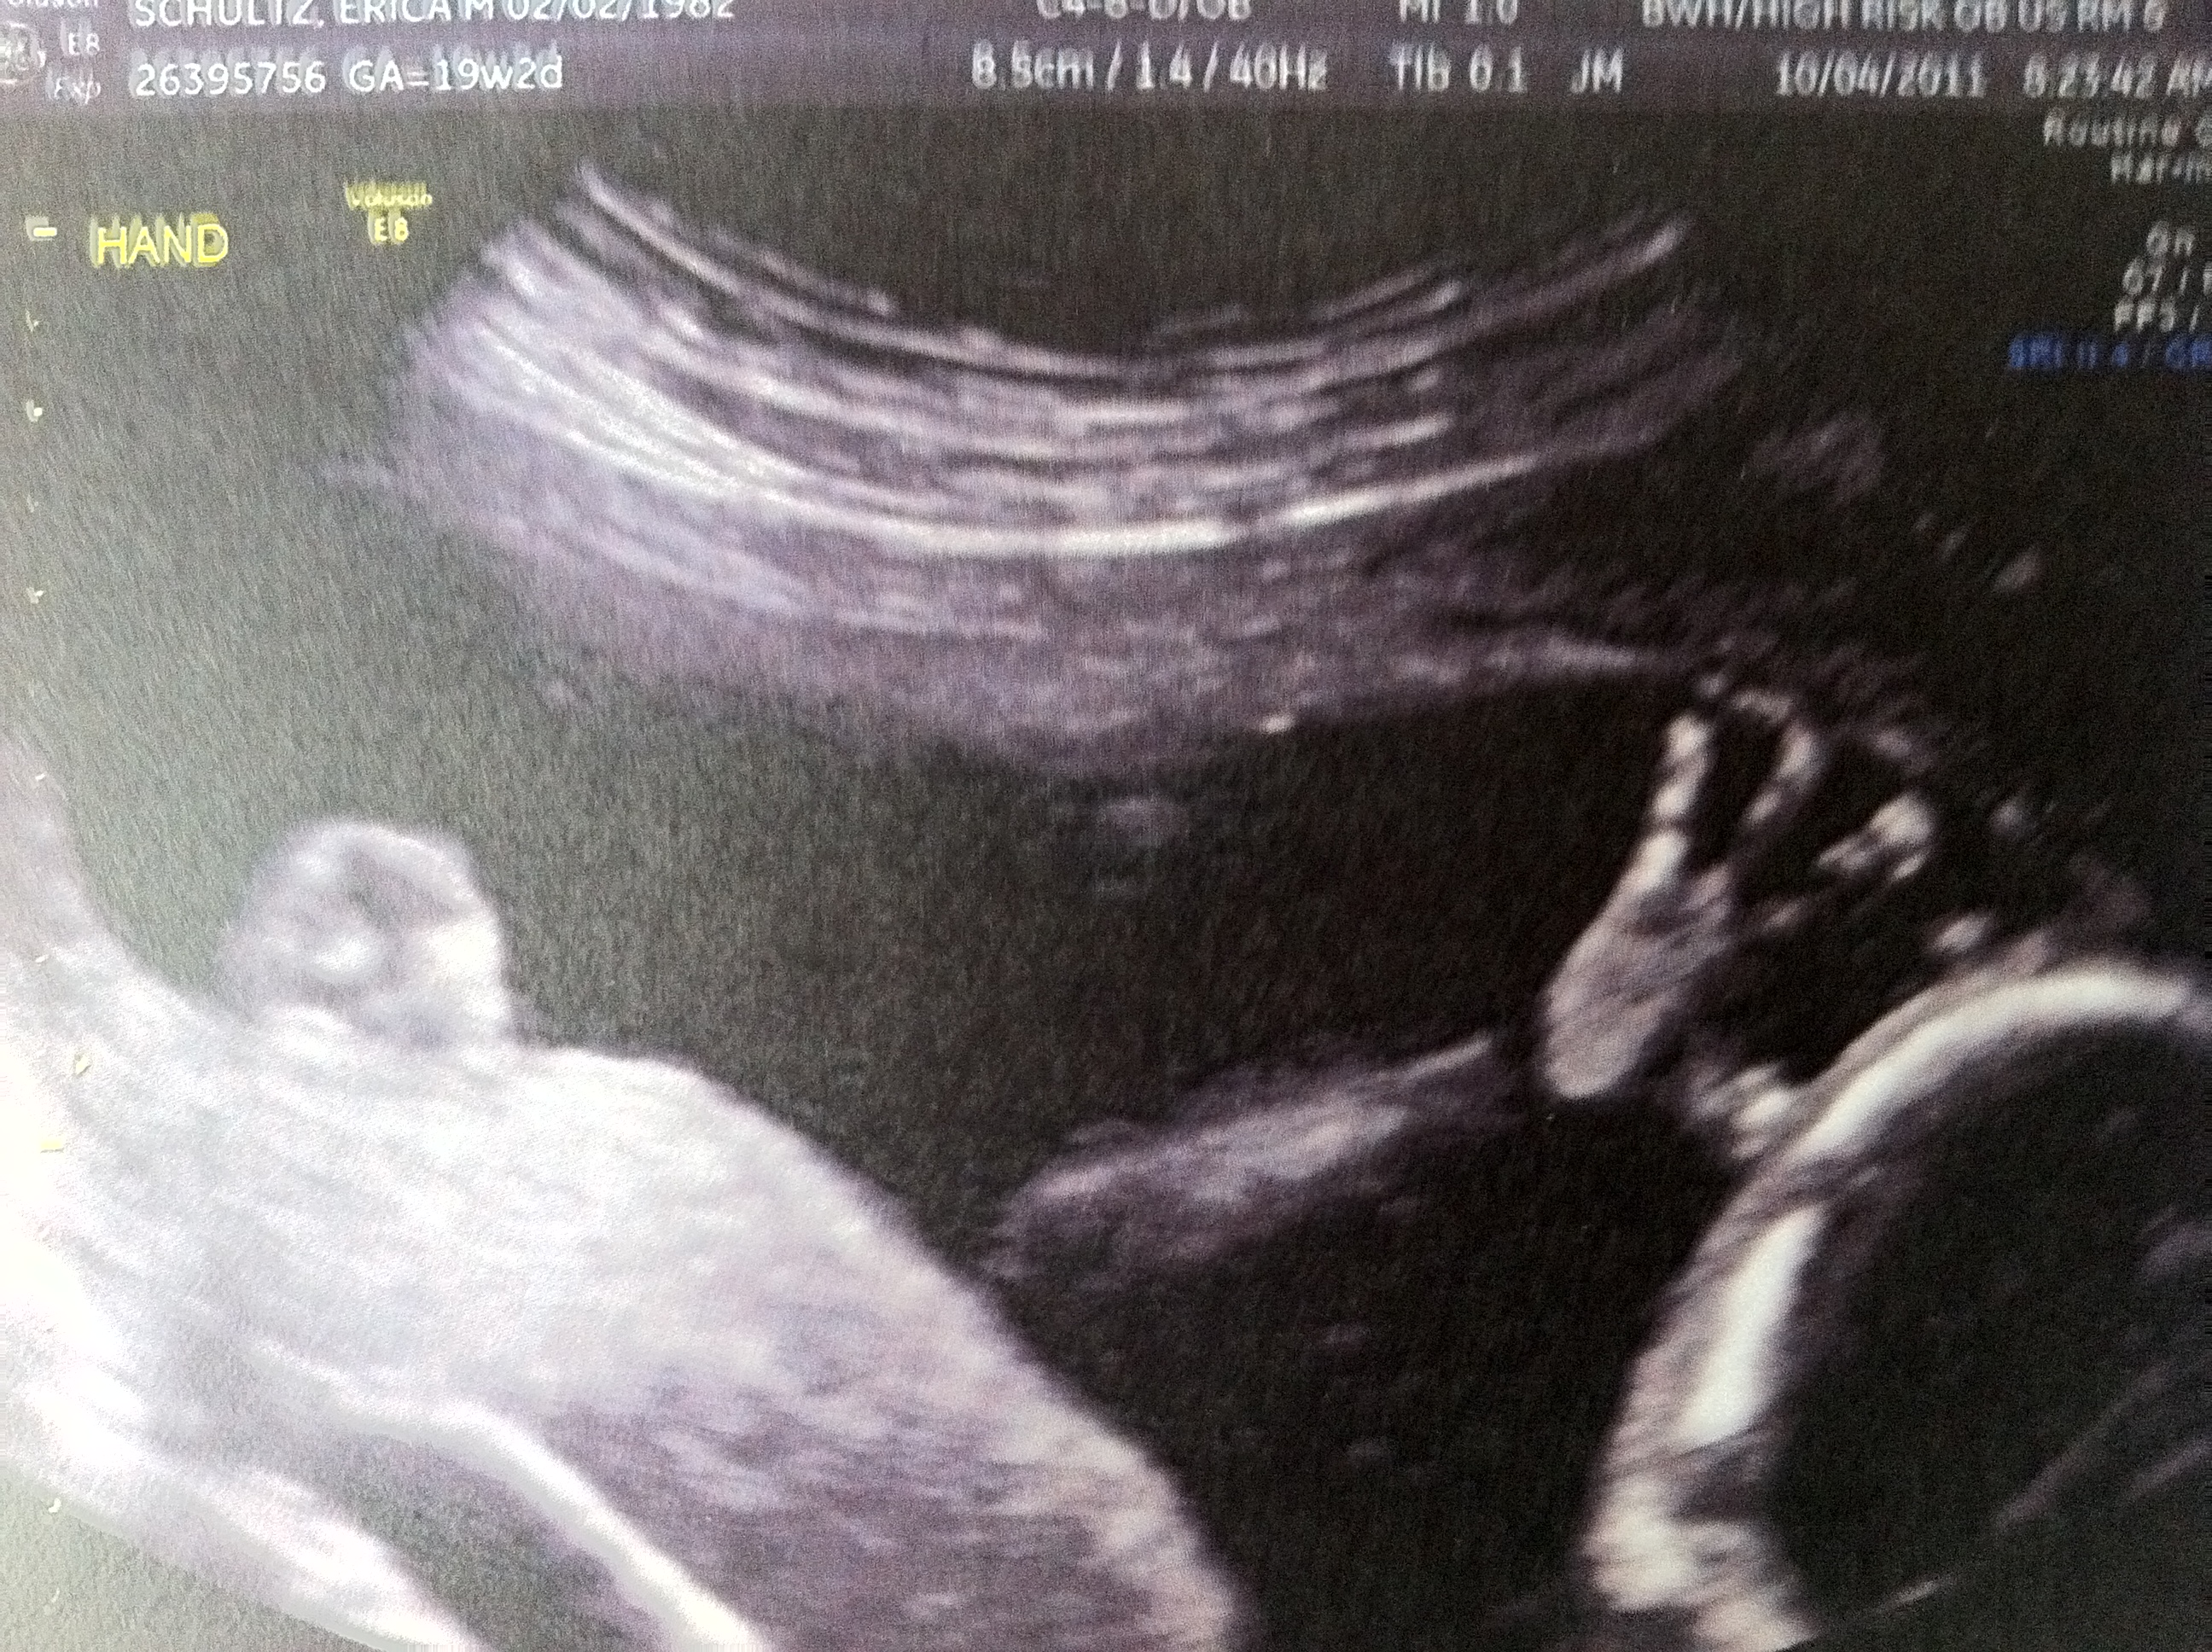

I’m Already a Thumb Sucker.